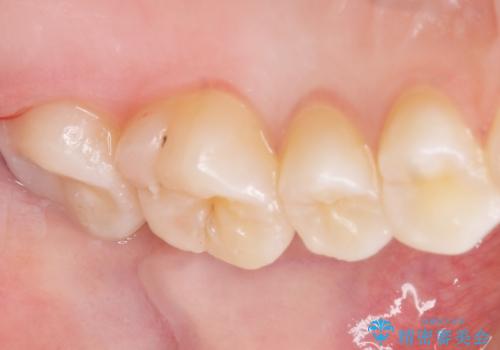

気づかなかった奥歯のう蝕 セラミックインレー 20代女性

- クリーニングを希望され来院された患者様です。

精査したところ、奥歯にう蝕を認めました。

症状がなく気がつかなかったそうで、虫歯があったことに驚かれていました。

患者様のご希望により、う蝕を丁寧に除去したのちセラミックインレーによる修復を行いました。